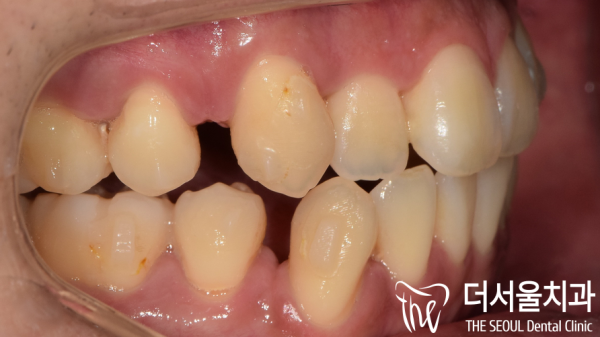

먼저 육안으로 환자분의 치아상태를 확인해보았습니다.

어금니가 아래쪽으로 많이 내려와 있었고, 치아가 반대교합으로

물리는 부분도 관찰되고 있습니다.

또한 전체적으로 치아가 앞으로 돌출된 입매를 보이는데요.

환자분께서는 #27 어금니를 교정하고 돌출된 입매와 삐뚤빼뚤한

치아를 전체적으로 교정하고 싶어하셨습니다.